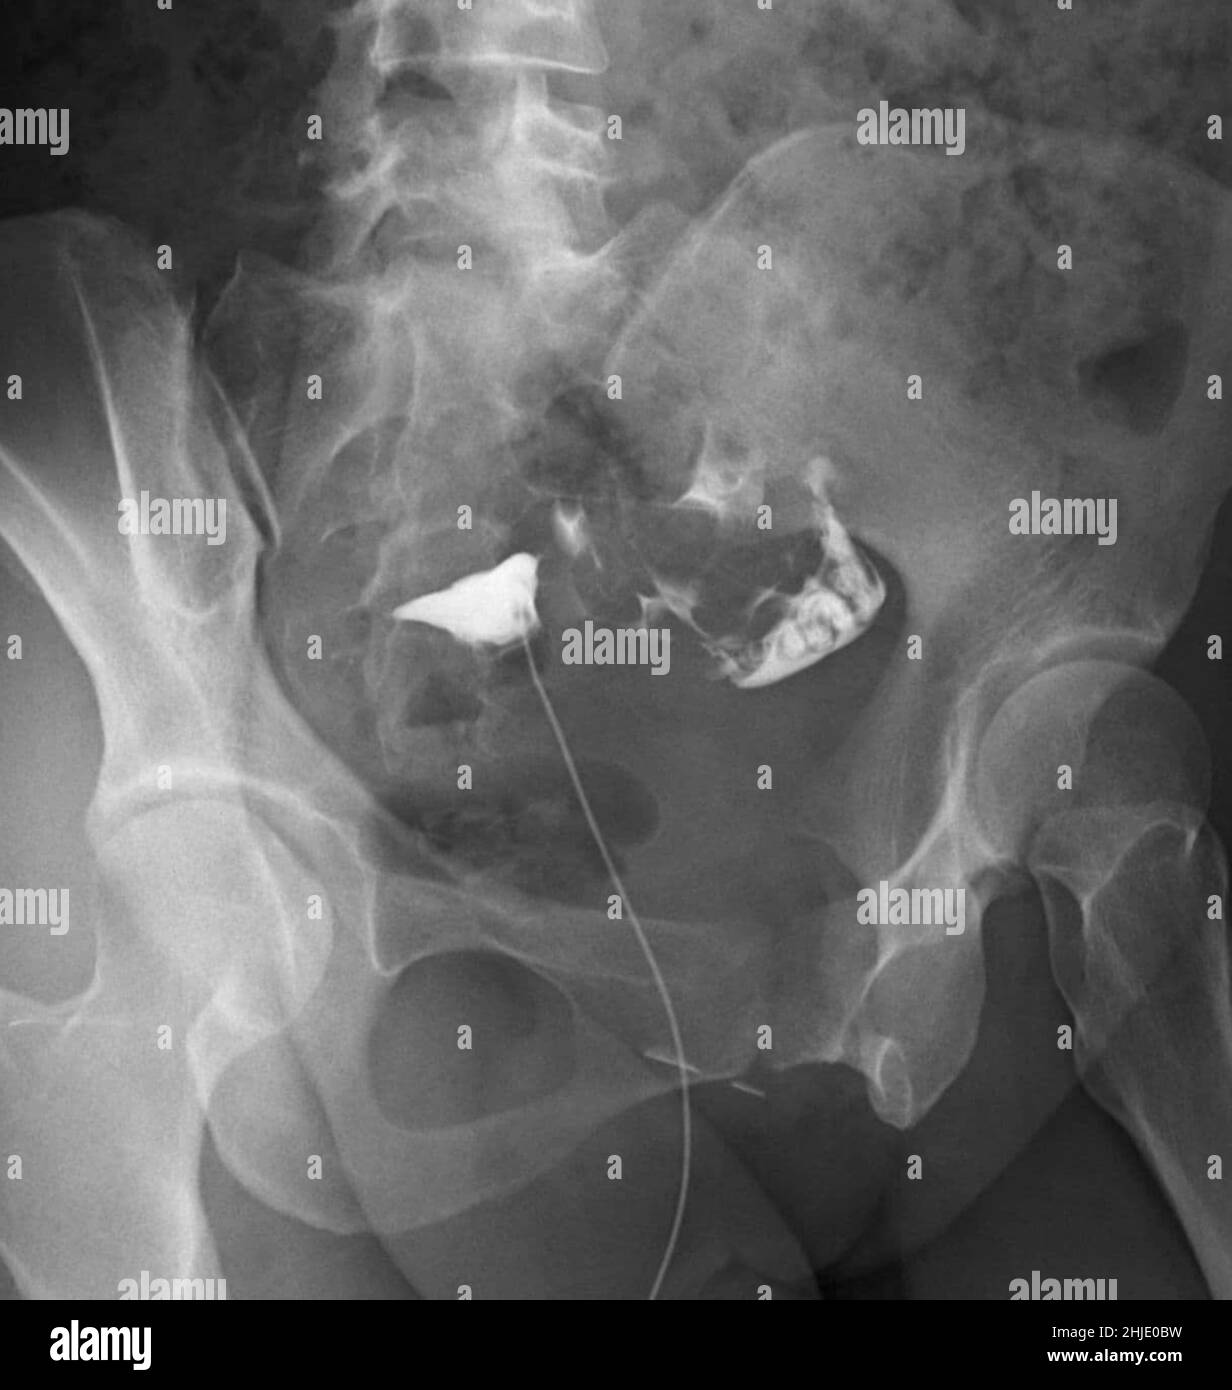

Fallopian Tube Clips X Ray . when placed across the isthmic portion of the fallopian tube, tubal ligation clips serve as a means of rapid and effective tubal occlusion [4]. Refer to the article on medical devices in the abdomen and. They commonly fall off the fallopian tubes and. On mdct, the metallic clips are identified as small hyperdense cylindric structures or as solid circular structures close to the body of the uterus (fig. the ability to differentiate fallopian tube conditions from other adnexal and pelvic pathologic entities by using a variety of imaging modalities allows the radiologist to make a timely diagnosis and ensure proper clinical management. surgical clips used in laparoscopic tubal ligation procedures. these large metallic staples are commonly seen in abdominal radiographs and are typical of tubal ligation clips. learn about the gross and microscopic anatomy, relations, blood supply, and radiographic features of the fallopian tube, a paired hollow tube.

Tubal ligation clips Radiology at St. Vincent's University Hospital Fallopian Tube Clips X Ray On mdct, the metallic clips are identified as small hyperdense cylindric structures or as solid circular structures close to the body of the uterus (fig. when placed across the isthmic portion of the fallopian tube, tubal ligation clips serve as a means of rapid and effective tubal occlusion [4]. They commonly fall off the fallopian tubes and. surgical. Fallopian Tube Clips X Ray.